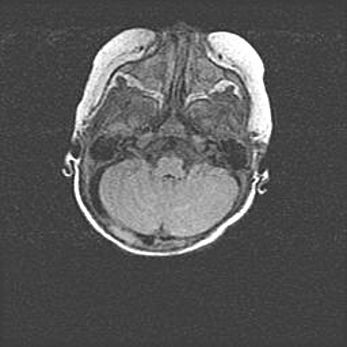

Наружная гидроцефалия с возможной атрофией височных областей.

Возраст: 28 дней

Вес: 3670 г

Пол: мужской

Окружность головы: 38 см

Срок гестации: 40 недель

Гидроцефалия головного мозга у новорожденных – это заболевание, которое характеризуется скоплением избыточного количества спинномозговой жидкости в желудочковой системе головного мозга в результате затруднения её перемещения от места выработки к месту поглощения в кровеносную систему или вследствие нарушения абсорбции. При открытой наружной форме гидроцефалии у новорожденных расширяются и переполняются субарахноидные пространства.

При нормотензивных  формах,  которые,  как  правило,  являются  следствием  перенесенных ишемических  повреждений  паренхимы  мозга,  возможно  сочетание микроцефалии  с нормотензивной гидроцефалией. В основе данных изменений лежит атрофия больших полушарий с преимущественной  локализацией  в  лобно-височных  областях.